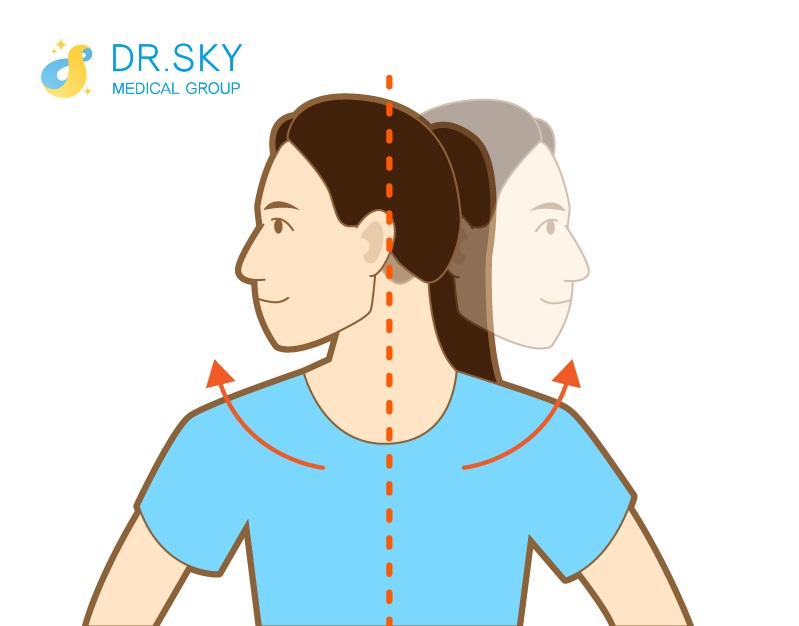

● 積極鍛鍊

可緩解筋肉疲勞,使肌肉韌度變好,有利於增強頸肩順應頸部動態變化的能力。

▲ 旋轉運動:旋轉頭部,視線看向肩膀後方,維持15秒後後回復起始姿勢。再換另一側,每一側做5次。